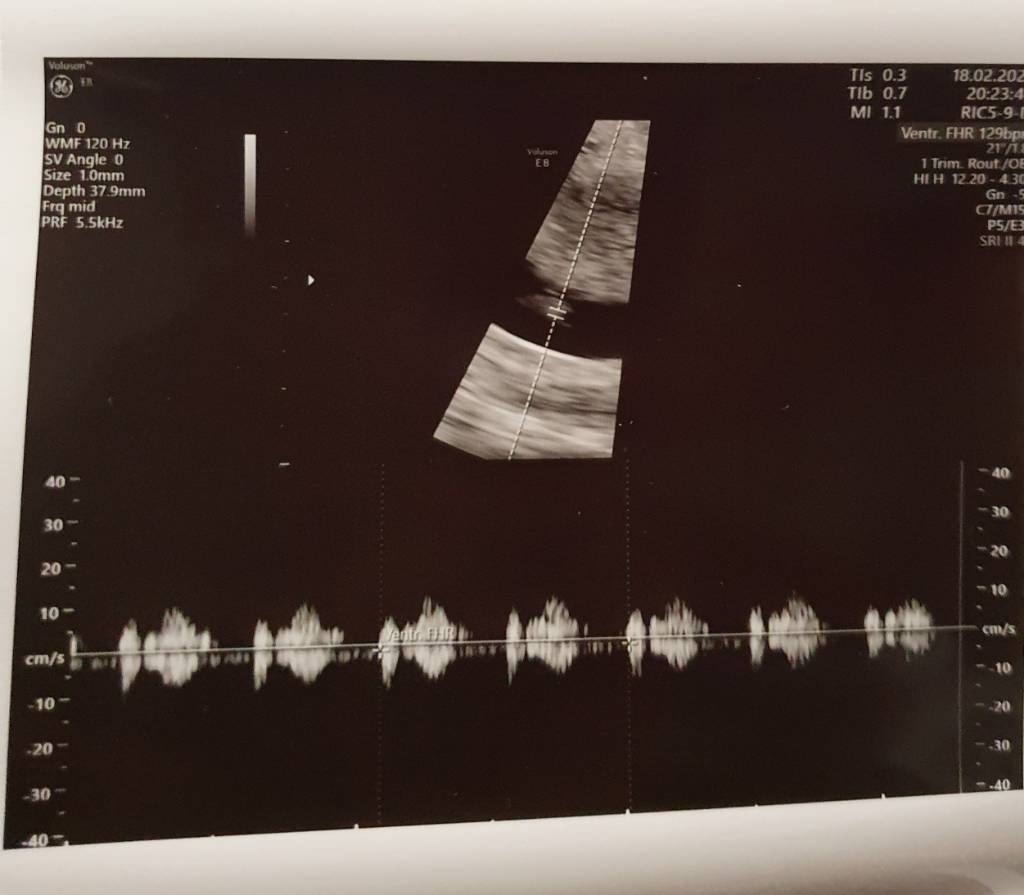

My też już po wizycie ❤ co prawda serduszko jeszcze nie bije- ciąża o wiele młodsza niż wychodziłoby z terminu ostatniej @- ale tego się spodziewałam, bo cykle nieregularne, następna wizyta w przyszły czwartek, liczymy że usłyszymy ❤, dzidzia ma prawie 3 mm- przełom 5/6 tygodnia. Dostałam progesteron, zwiększamy dawkę Euthyroxu- jutro idę na badania plus krzepliwość bo wcześniej miałam z nią problemy.

My też już po wizycie [emoji173] co prawda serduszko jeszcze nie bije- ciąża o wiele młodsza niż wychodziłoby z terminu ostatniej @- ale tego się spodziewałam, bo cykle nieregularne, następna wizyta w przyszły czwartek, liczymy że usłyszymy [emoji173], dzidzia ma prawie 3 mm- przełom 5/6 tygodnia. Dostałam progesteron, zwiększamy dawkę Euthyroxu- jutro idę na badania plus krzepliwość bo wcześniej miałam z nią problemy.